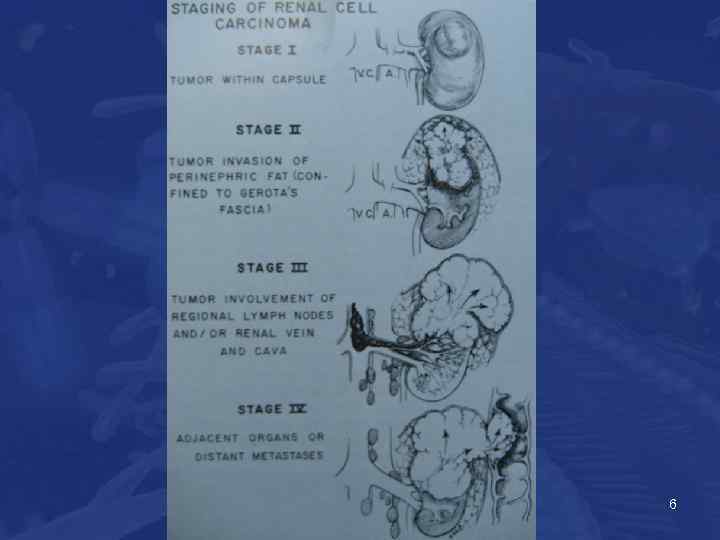

Классификация (TNM) • T 1 опухоль размерами до 7 • T 2 опухоль размерами >7 cm • T 3 опухоль вовлекает большие сосуды или надпочечник • T 4 опухоль распространяется за проделы Gerot’s fascia • N 1 вовлечен один лимфоузел • N 2 более одного 5

6